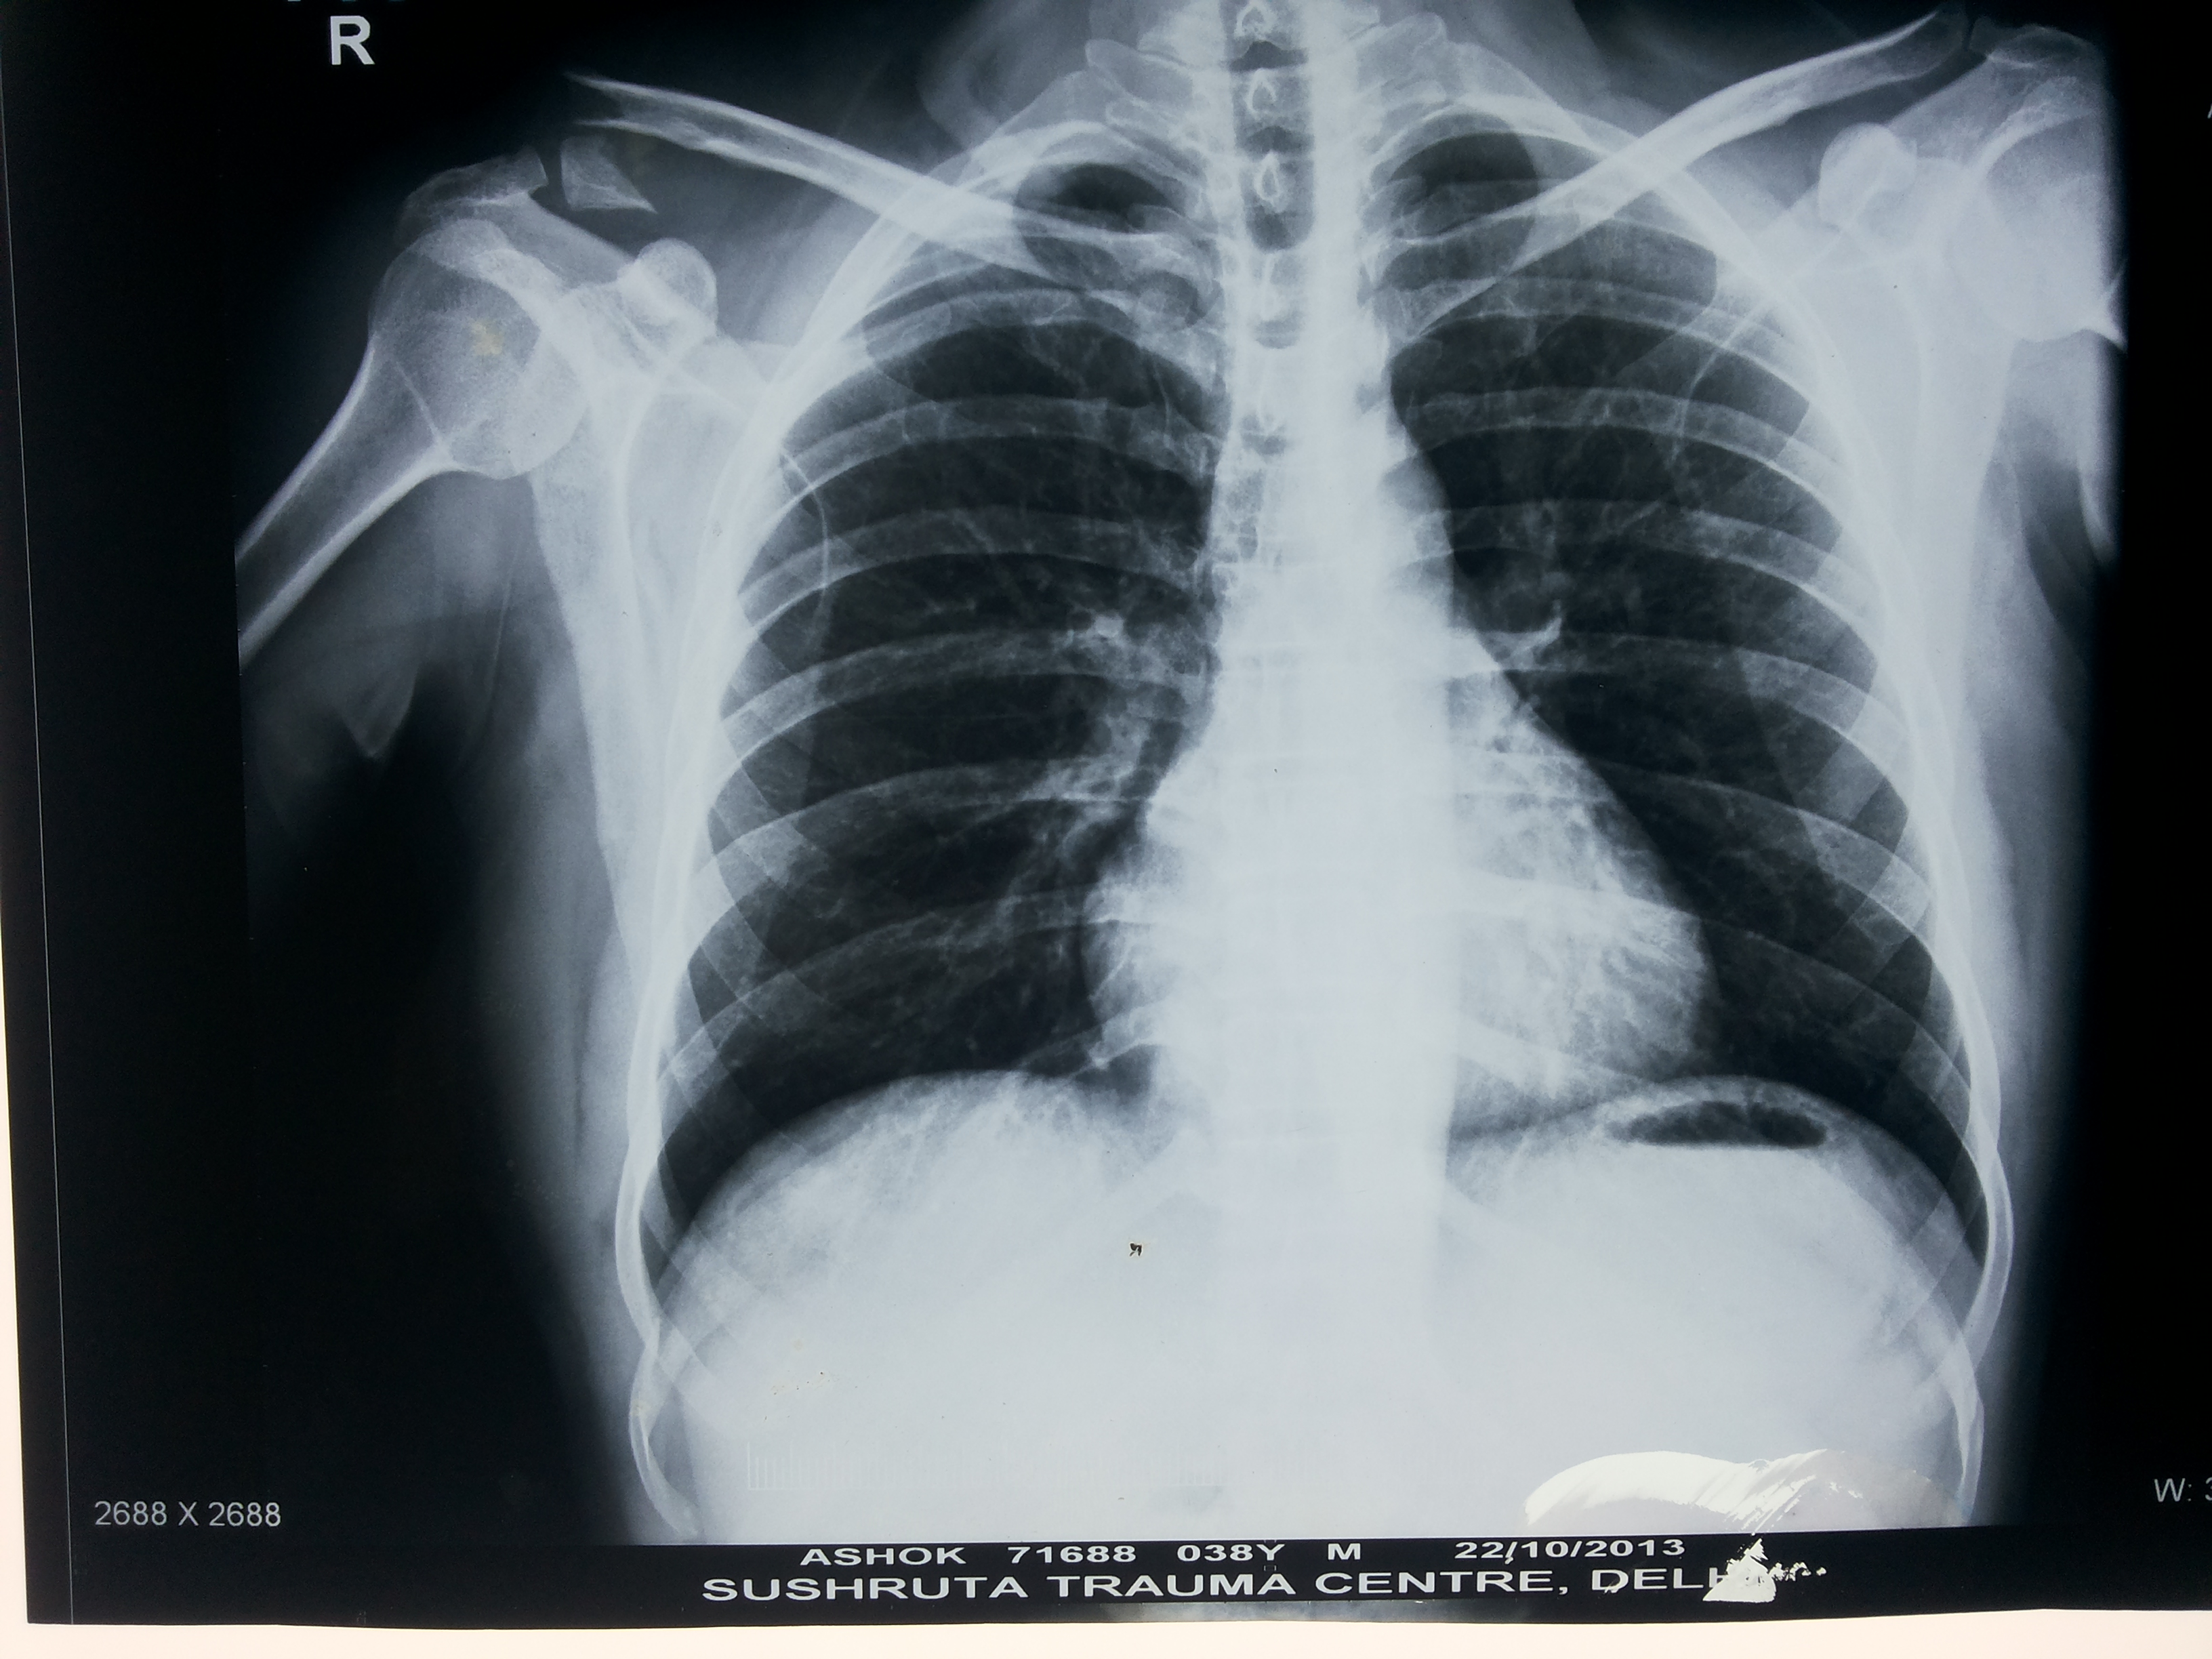

In order to determine the cause of a fracture, a doctor will inquire about the circumstances involved. A physical examination will then be performed to determine the cause. They will often order an X-ray and, in some cases, an MRI or CT scan in order to fully assess the fracture.